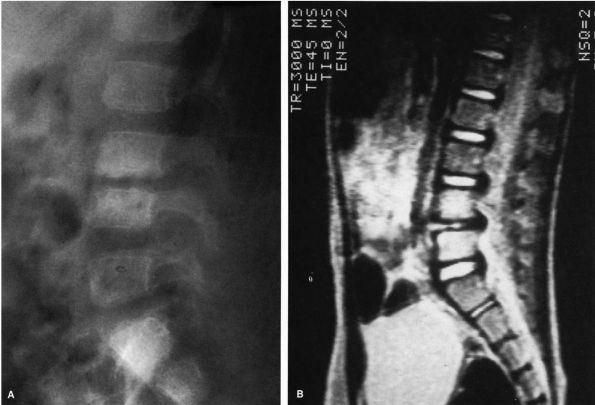

not be excluded because of a normal bone scan. MRI has been shown to be

able to accurately demonstrate an abnormal disc space, and we have

recently demonstrated that the MRI is abnormal before the bone scan is

positive and before radiographic changes are evident (Figure 5-11).

![]() |

FIGURE 5-11.

MRI of the spine demonstrating an abnormal L4-L5 disc. Note the loss of height and the change in the density of the disc. The bone scan, the plain radiographs, and the lateral tomograms of this patient were normal. The lateral radiograph of the spine subsequently demonstrated the typical changes seen in disc space infections. |